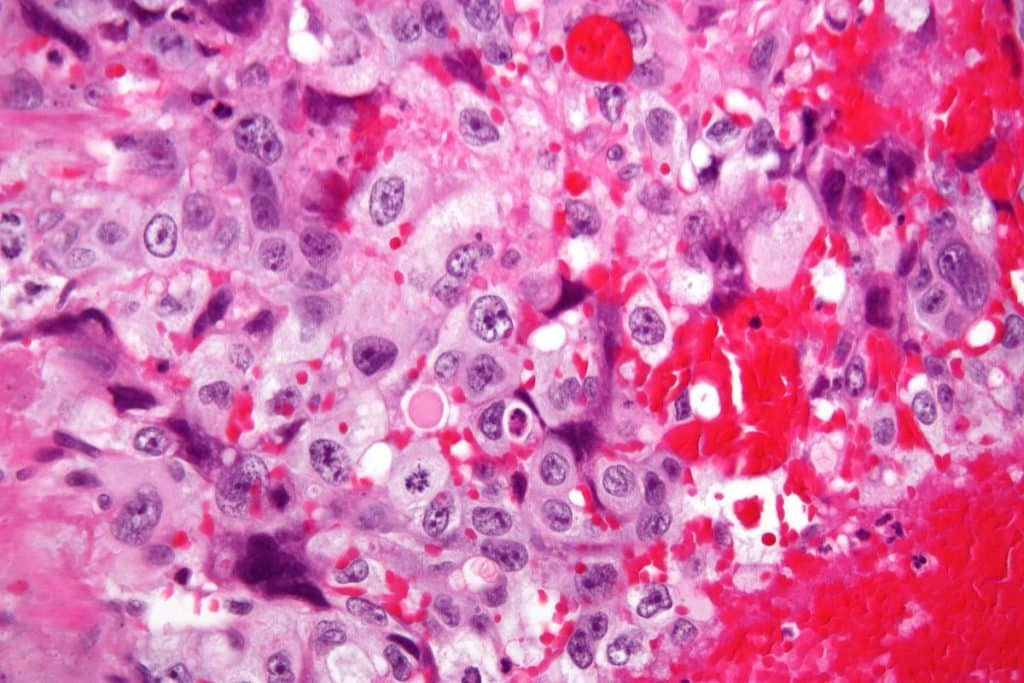

• Ultrasound Scan – a complete mole has a granular or snowstorm appearance with a central heterogeneous mass and surrounding multiple cystic areas/vesicles.

Fig 2 - Complete mole on transabdominal ultrasound of the pelvis. The uterus (arrow) is shown with multiple cystic areas within an enlarged echogenic endometrial cavity (arrowhead).

Complete mole on transabdominal ultrasound of the pelvis. The uterus (arrow) is shown with multiple cystic areas within an enlarged echogenic endometrial cavity (arrowhead).